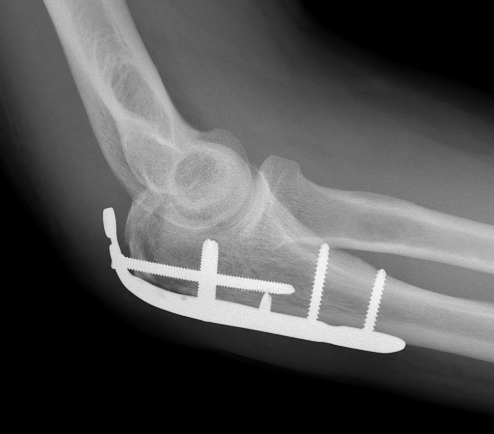

ORIF with olecranon plate

Indication

Fracture distal to center of rotation of elbow / trochlea

Technique

Lateral decubitus with tourniquet

- curvilinear incision to avoid prominence of olecranon

- identify and protect ulna nerve

- reduce fracture with arm in extension

- ensure articular congruity

- use anatomical precontoured plate

- may want to split distal triceps to reduce proximal plate prominence